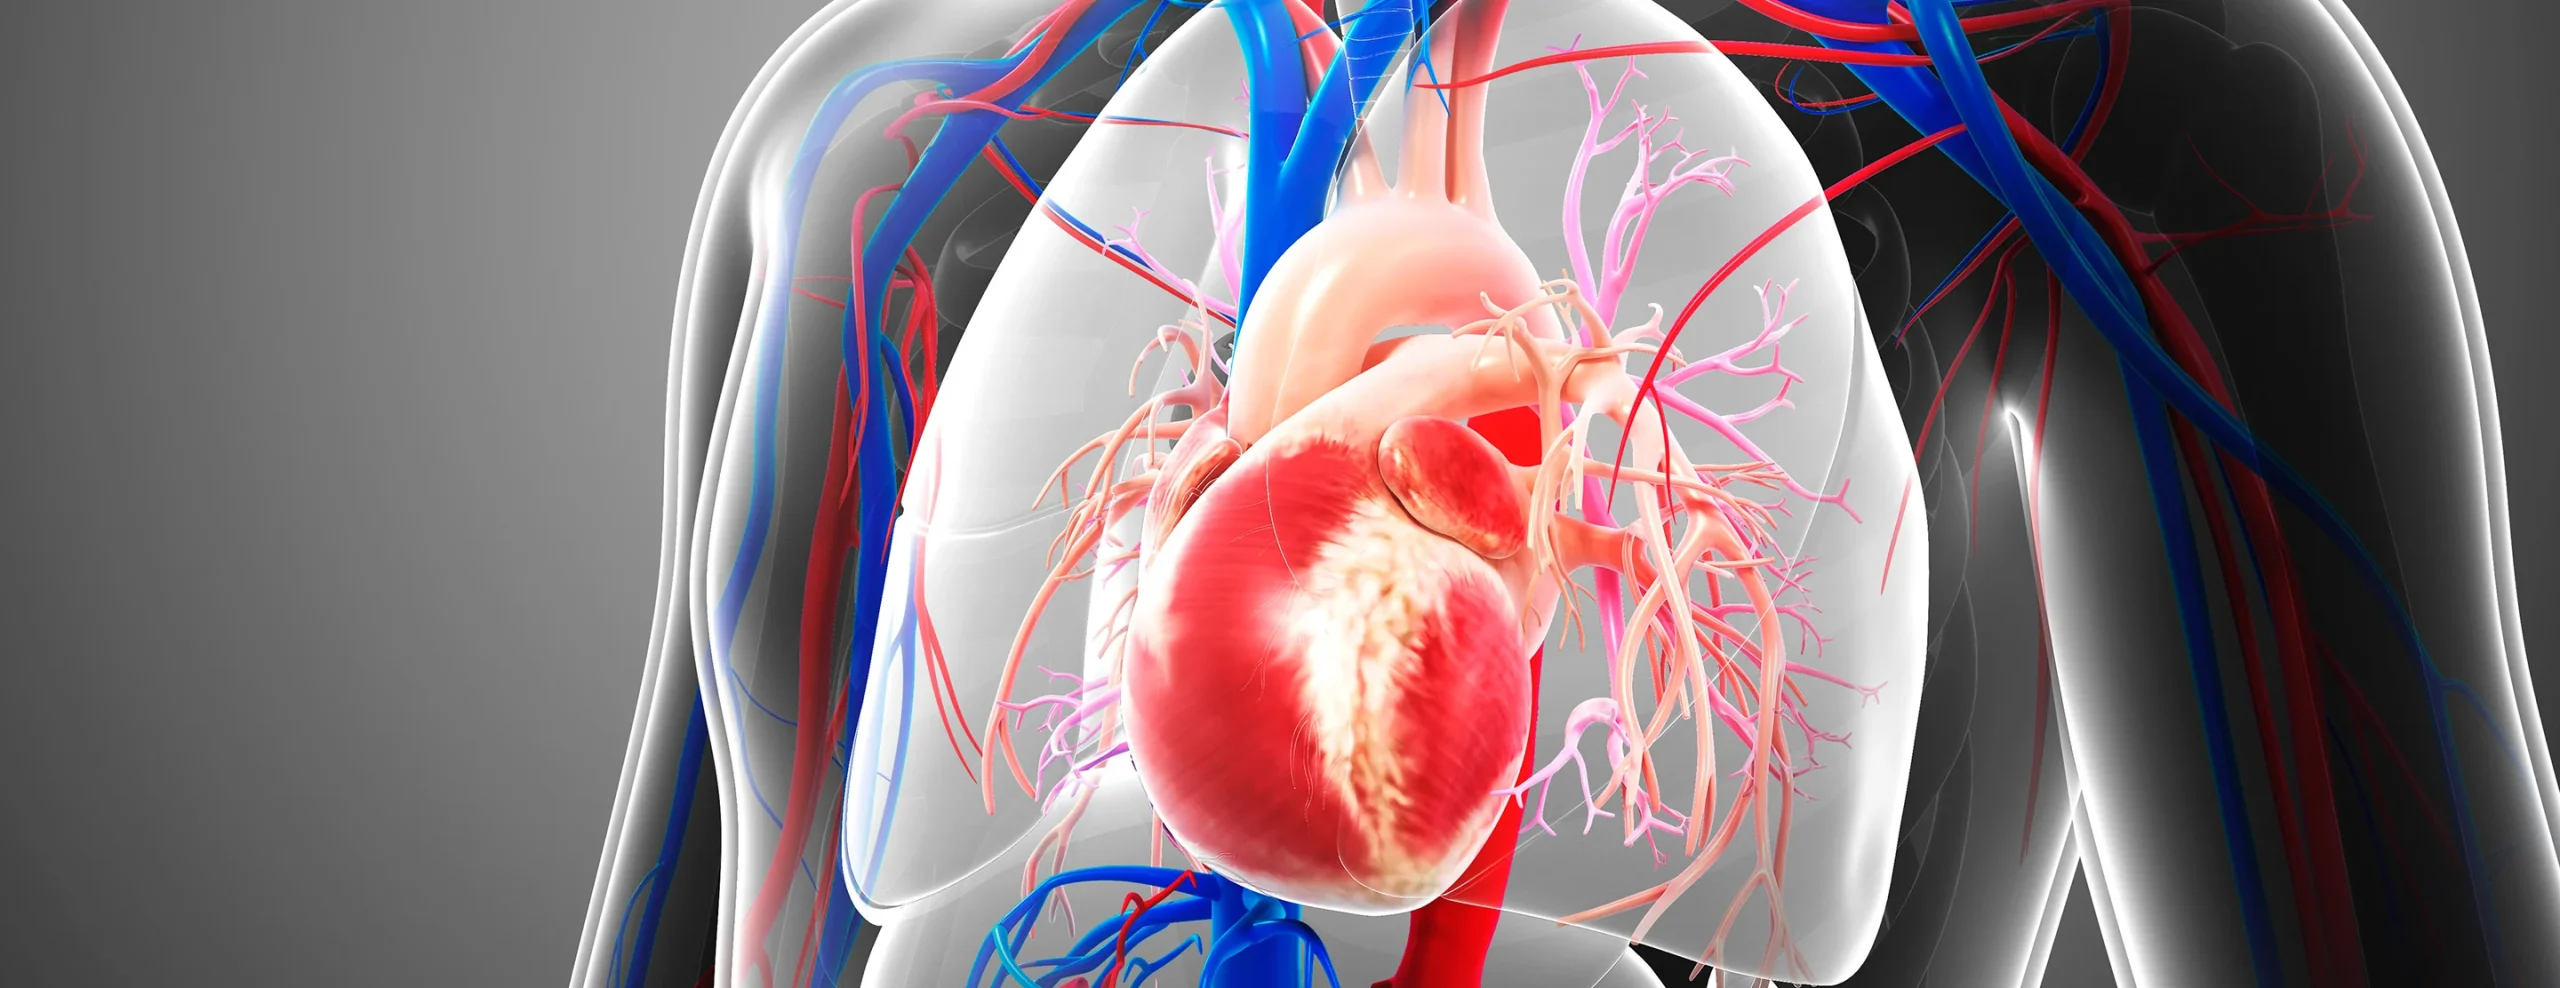

العقدة الجيبية الأذينية

تُعرف بالعقدة الجيبية، وتُعد المنظم الطبيعي لضربات القلب. تقع في الأذين الأيمن، وتولد نبضات كهربائية منتظمة تبدأ منها عملية انقباض القلب.

انتقال الإشارة إلى الأذينين

تنتشر الإشارة الكهربائية من العقدة الجيبية إلى الأذينين، مما يؤدي إلى انقباضهما ودفع الدم إلى البطينين.

العقدة الأذينية البطينية

تنتقل الإشارة إلى العقدة الأذينية البطينية، حيث يحدث تأخير بسيط يسمح بامتلاء البطينين بالدم قبل انقباضهما.

حزمة هيس وألياف بوركنجي

تمر الإشارة بعد ذلك عبر حزمة هيس وألياف بوركنجي لتصل إلى البطينين، مما يؤدي إلى انقباضهما وضخ الدم إلى الرئتين وبقية الجسم.

عندما يعمل هذا النظام بانسجام، يكون النبض منتظمًا وطبيعيًا. أما في حال حدوث خلل، تظهر اضطرابات كهرباء القلب.